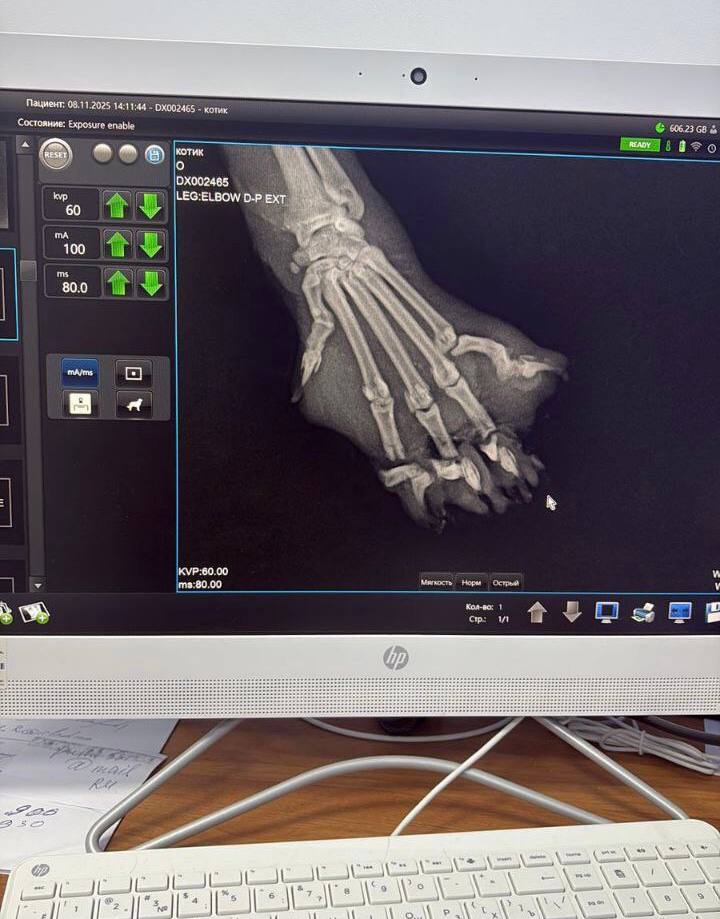

В Министерстве сельского хозяйства и продовольствия Московской области сообщили, что обследование кота показало серьезные повреждения. Капкан пережал три пальца на передней лапке, а при попытке животного освободиться конструкция частично сняла кожный покров с конечности. В связи с необратимыми повреждениями тканей и для спасения жизни кота было принято непростое, но необходимое решение — провести ампутацию трех пережатых пальцев. Операция требовала высочайшей точности и профессионализма из-за обширной зоны повреждения мягких тканей.